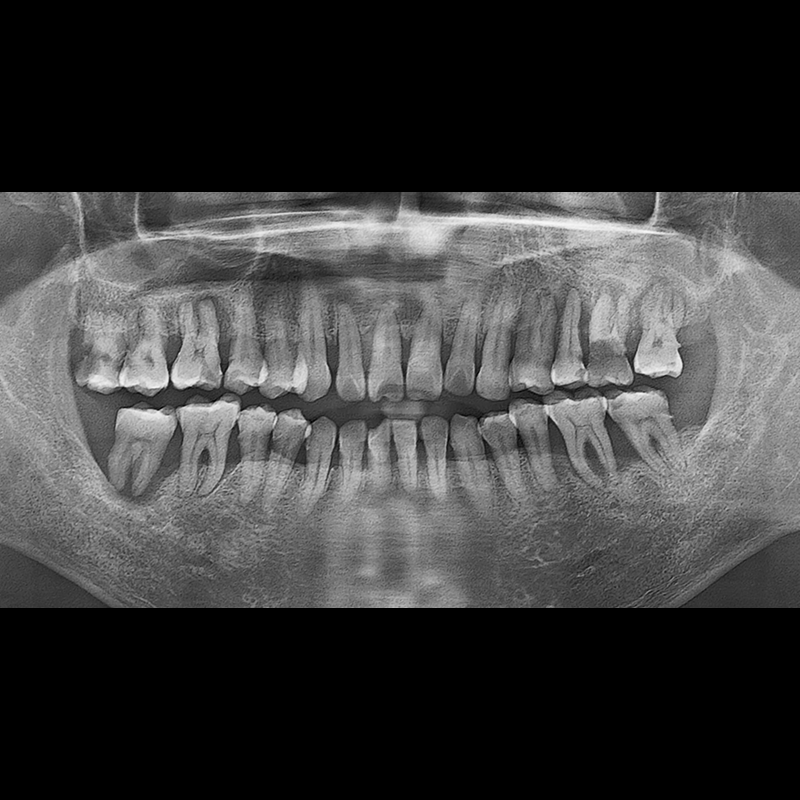

IMPLANT

BEFORE AFTER

种植牙前后的照片 2025.05.30

在缺失的牙齿部分和难以挽救的牙齿位置植入了种植牙。